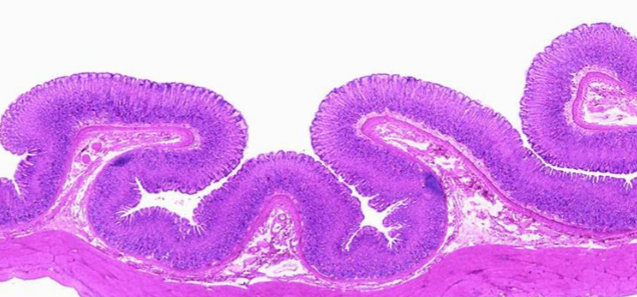

What are the permanent folds in the small intestine called?

Plicae circulares

What are rugae and why are they needed?

Rugae are temporary folds in the stomach which allow it to expand